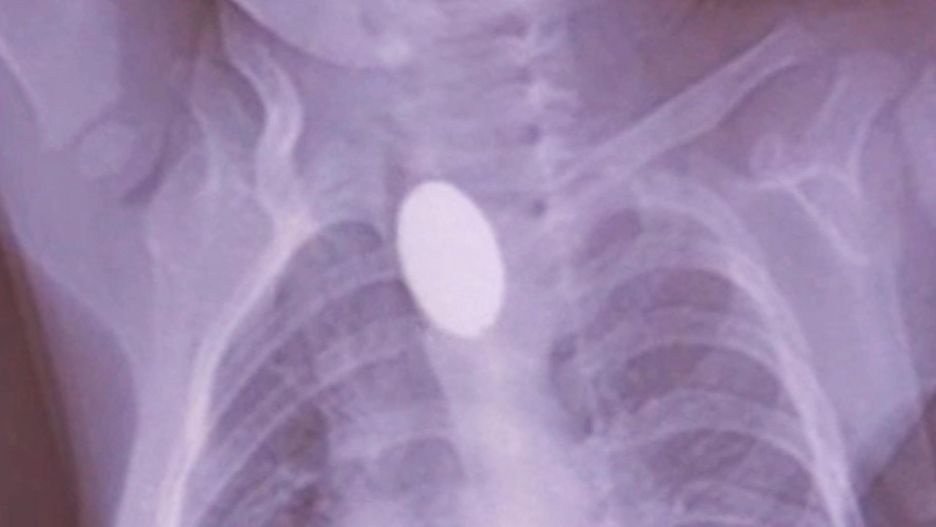

Mama chłopca nie zauważyła, co się stało, ale gdy tylko zorientowała się, że coś jest nie tak, zabrała go do szpitala uniwersyteckiego Elazig Firat. W przeprowadzonej kontroli stwierdzono, że bateria utknęła w przełyku i spowodowała oparzenie. Wkrótce podjęto dezycję o usunięciu jej metodą endoskopową.

Dr Yasar Dogan, który zajął się chłopcem, zamarł, gdy wykonał rentgen. Wiedział, że musi działać szybko. Na szczęście był w stanie wyjąć przedmiot z jego przełyku za pomocą endoskopu, ale zauważył, że malec doznał oparzeń w miejscu, w którym bateria się zatrzymała.

"Zauważyłem poważne oparzenia przełyku po usunięciu baterii metodą endoskopową. Zostanie wprowadzona specjalna metoda karmienia, tak by móc kontrolować stan gojenia ran dziecka, czy nie wystąpi infekcja"- powiedział dr Dogan.